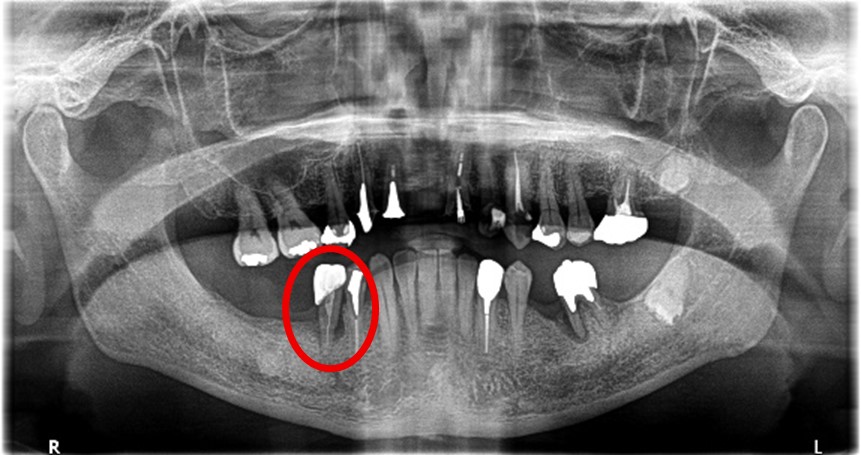

Before

※赤丸を抜歯しました。

歯根の周りの骨が全く無い状態でしたので、保存することができず抜歯しました。3本歯がないところに2本インプラントを埋入しました。

所感

抜歯後、歯がなくなったところを補う方法には、部分入れ歯とインプラントがあります。この症例の場合、右下以外ほとんど歯が残っていますので、もし部分入れ歯にした場合、入れ歯のところで他のところと同じ感覚で噛むことができないので、慣れることが大変です。また部分入れ歯の支えになっている歯に負担がかかりますので、今後さらに歯を失う可能性が大きくなります。インプラントは、自分の歯と同じ感覚で噛むことができ、単独で植立していますので他の歯に負担がかかることがありませんので、更に歯を失うことを防ぎます。